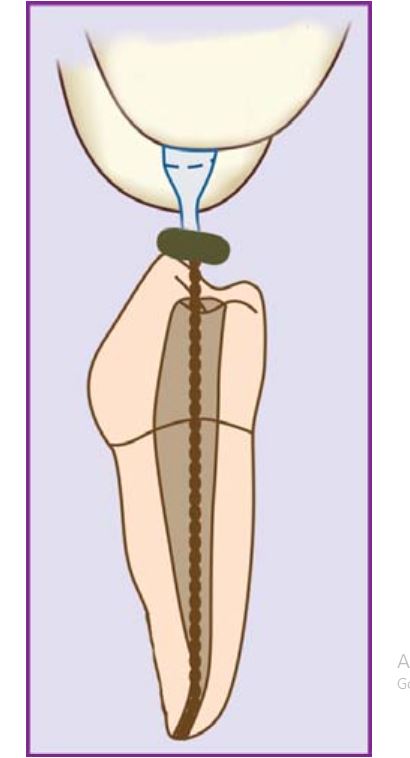

Có thể xác định độ sâu trần tủy bằng cách đặt mũi khoan lên phim để ước lượng (H5.3).

Khi đã có cảm giác hẫng tay thì chứng tỏ phần trần tủy đã thủng, nên sử dụng các mũi khoan có đầu tận cùng an toàn để tiếp tục (H5.4).